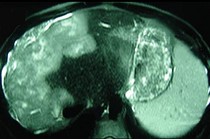

- 单项选择题女性,72岁, 腹胀不适1年,加重伴恶心、呕吐、乏力1个月, 影像检查如图,最可能的诊断为  (    )

- A、肝硬化腹水

- B、原发性肝癌

- C、肝血管瘤

- D、巴-希综合征

- E、局灶脂肪肝